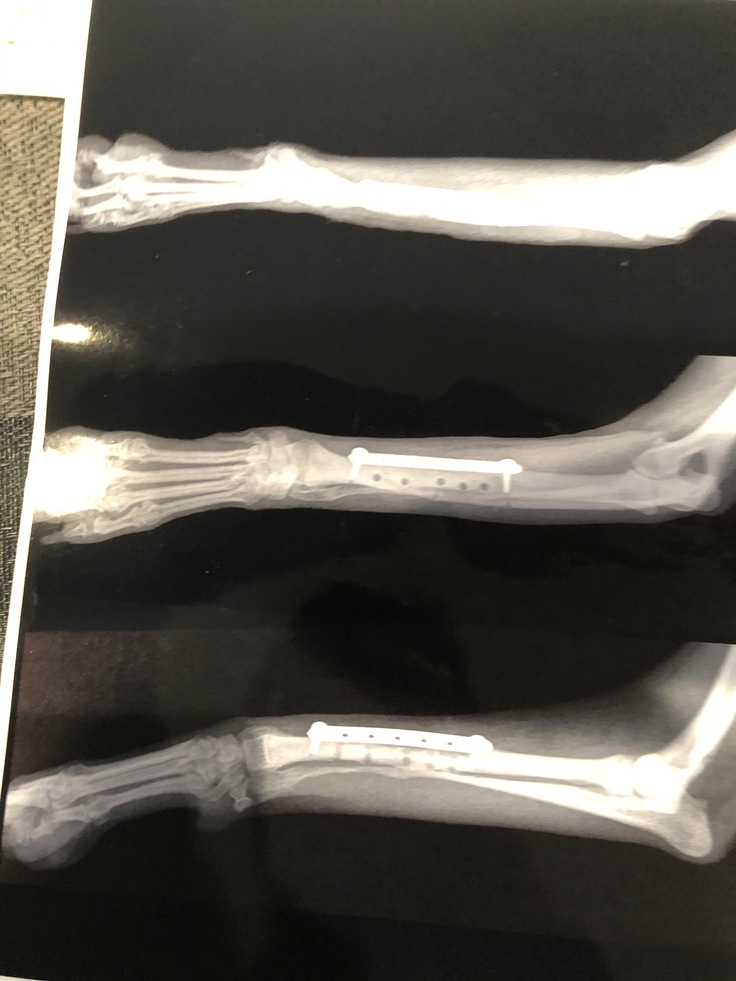

手術内容としては、骨をプレートとボルトで固定する手術でした。

原因としては最初の病院で入れたプレートのサイズがあり得ないほど大き過ぎる上にボルトの位置が不適切で骨の再生の邪魔をしてるとの事。

すぐに適切なサイズのプレートと入れ替え、大きく開いたスクリューホールに骨の組織を移植する手術がはじまりました。

手術は無事終わり、術後のレントゲンを見ると大きなスクリューホールが…

いかに大きいサイズのプレートが入っていたのか分かりました。

↓最新のレントゲン写真です